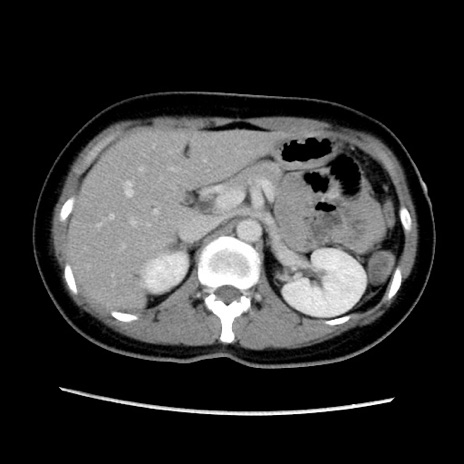

症例39(横断像)

【症例】40歳代女性

【主訴】上下腹部痛

【現病歴】2日目から下腹部痛あり。夜間は痛みで眠れなかった。昨日より上腹部痛と下痢が出現。臥位で痛みは軽快したため、休んでいた。本日になって臥位でも立位でも痛みが強くなってきたため救急要請。

【既往歴】子宮内膜症

【身体所見】部:平坦・軟、左上下腹部に圧痛あり、反跳痛あり。

【データ】WBC 21800、CRP 26.78